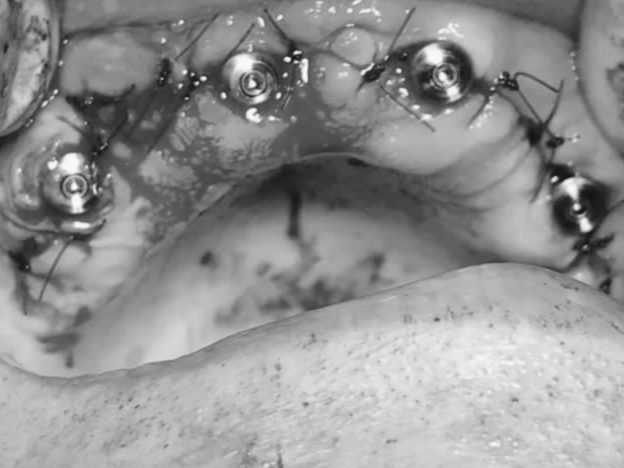

Для восстановления зубного ряда в области верхней или нижней челюсти проводят all-on-4 имплантацию. Среди главных преимуществ процедуры выделяют то, что стоматолог устанавливает несъемный протез, состоящий из 12 единиц, который прочно фиксируется в области корня. Для этого устанавливают штифты в переднем отделе под прямым углом. Также вживляют боковые импланты под углом, чтобы обеспечить равномерное распределение жевательной нагрузки на зубной ряд.

Имплантация зубов под ключ в стоматологии Софи-Стом проводится одномоментно или в несколько последовательных этапов. Специалисты клиники перед операцией составляют подробный план диагностики и лечения, чтобы минимизировать риск развития осложнений. Стоимость услуги можно узнать на первичном стоматологическом приеме.